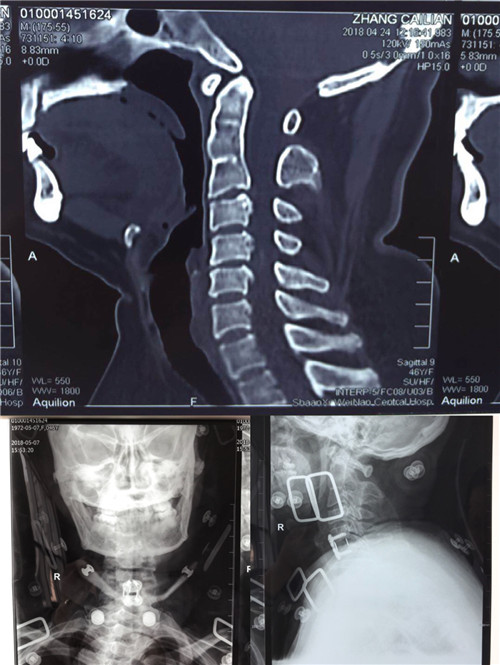

术后

尽管术中操作空间狭小,暴露不是那么充分,但经过细致耐心的剥离显露,小心谨慎的操作,最终顺利于5月4日完成了此例高难度手术,摘除了游离的蜕变髓核,切除了创伤后形成的机化瘢痕,实现了椎管容积的恢复、脊髓的减压,完成了融合器的植入,前路钢板螺钉的固定。术后患者症状改善明显,左侧肢体麻木,活动不灵便现象显著减轻,目前已经在支具的保护下下地活动。